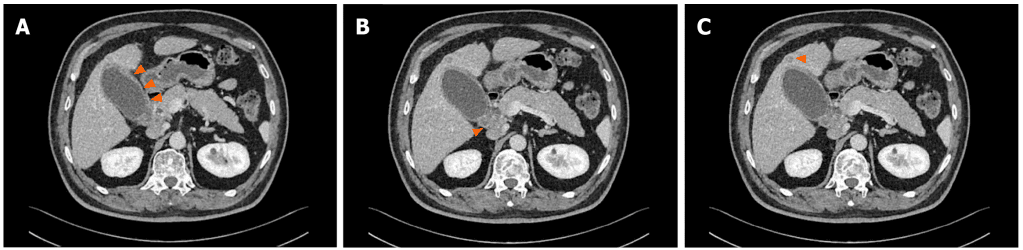

影像学检查:多期增强 CT(MCCT)显示胆囊体积增大、胆囊壁增厚,提示可能为胆囊炎;同时肝十二指肠系膜淋巴结肿大,肝 S4 段低密度灶,提示可能存在转移(图 1)。

图 1. 治疗前 MCCT检查结果

(A:胆囊体积增大、胆囊壁增厚;B:肝十二指肠系膜淋巴结肿大;C:稍低密度灶)